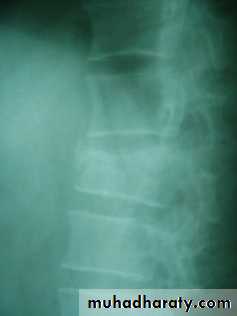

Fracture calcaneum

Fracture calcaneum and associated wedge fracture body of the vertebra

X- ray in lateral and axial view may shows chip, split, or crush fractures, CT sometimes used to assess the fracture details.